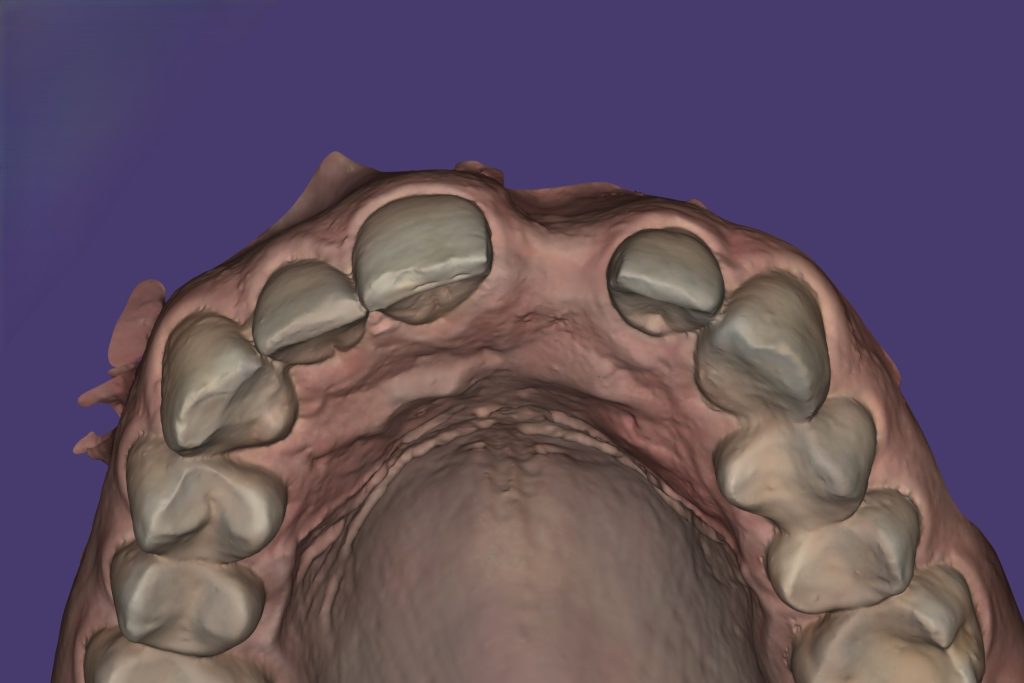

Intraoral Scan – clearly visible horizontal bone defect